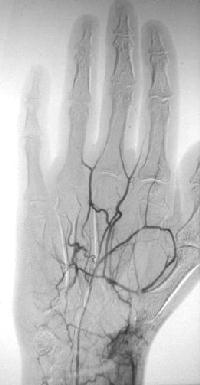

Case 3: More focal problem, thumb and index ischemia: Arteriogram:

Click for larger image